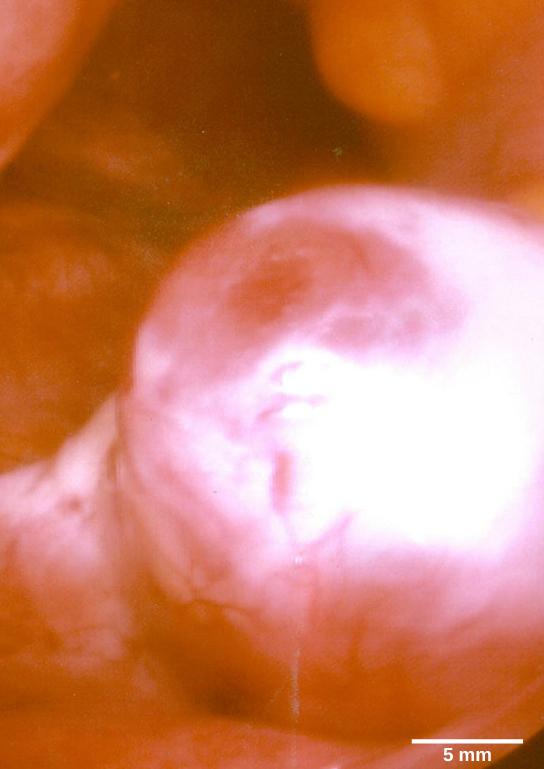

Just before the middle of the cycle (about day 14), the high level of estrogen causes FSH and especially LH to rise rapidly, then fall. The spike in LH causes ovulation: the most mature follicle, like that shown in Figure 34.18, ruptures and releases its egg. The follicles that did not rupture degenerate and their eggs are lost. The level of estrogen decreases when the extra follicles degenerate.